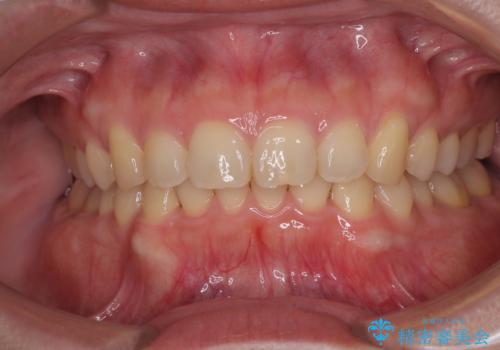

隠れた前歯が気になる ディープバイトのワイヤー矯正治療

下顎臼歯を起き上がらせるためにユーティリティーアーチを使用し、一気に深い咬み合わせを改善することができました。